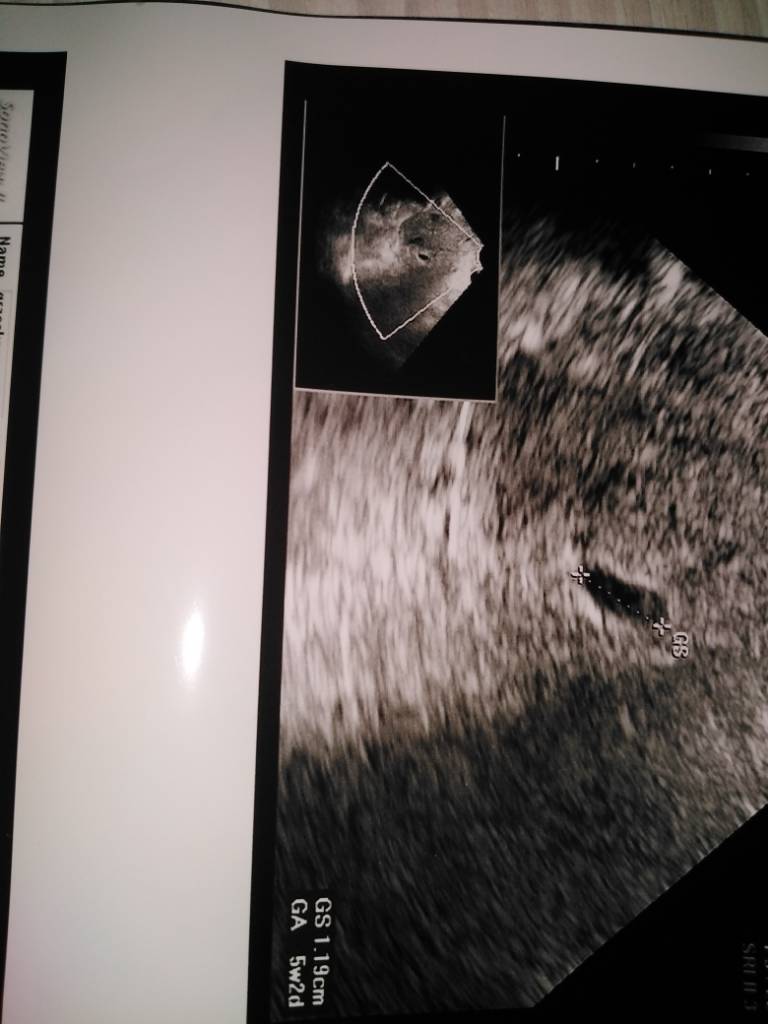

Jest tylko pecherzyk ciazowyA jest ciało żółte?

Nie nie ma zarodkaCzyli nie ma jeszcze zarodka ? Tak? Na to wychodzi.Ale ja bym na Twoim miejscu poszła do innego gina.Po moim ostatniej wizycie na izbie przyjęć byłabym ostrożna co do kierowania się opinią jednego lekarza.

Idź dla pewności gdzie indziej.Ja wiem sama po sobie ,że już bym nie zaufała jednemu lekarzowi...Nie nie ma zarodka